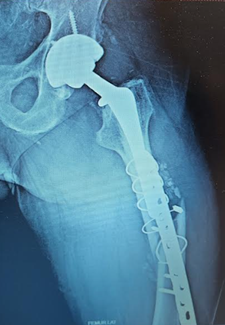

Second fixation, that's a lot of metal, including a few broken screws. Second photo shows healing callus